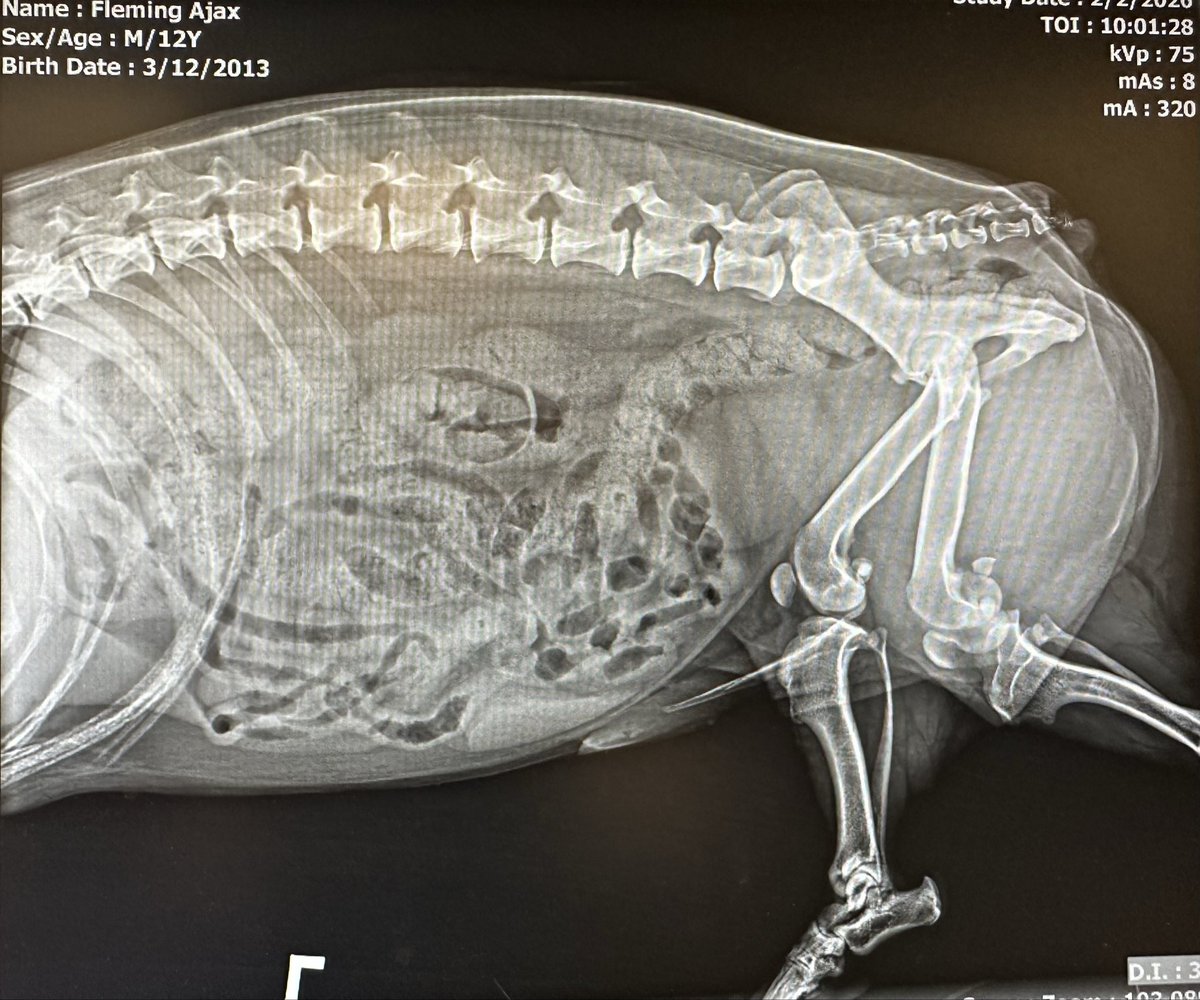

In case anybody was curious what a Corgi's L-spine and hips look like under x-ray. I was. #CorgiRad